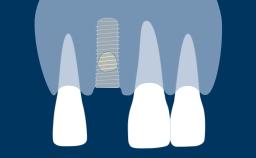

When a tooth is extracted, the alveolar bone that supports the tooth resorbs over time. This resorption results in a reduction in alveolar bone volume, as shown in this clinical example of a missing upper right central incisor. The bone has diminished significantly in orofacial width, and this is in conflict with the fundamental requirement in implant dentistry that implants are placed in the correct prosthodontically determined position. When the alveolar bone resorbs, it is often necessary to augment the bone to ensure that implants can be placed correctly and be completely embedded in bone. This module will describe a specific technique for bone augmentation known as guided bone regeneration or GBR.